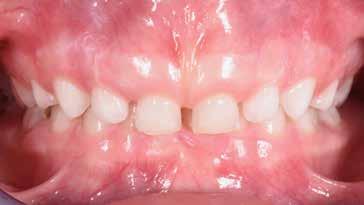

Presentazione del caso > F.V, bambino di cinque anni, presenta una malocclusione di II Classe scheletrica, III Classe dentale molare e canina destra e sinistra, morso inverso anteriore. Le arcate dentali mostrano usura degli elementi dentari anteriori a causa dell’occlusione patologica. Le linee mediane, superiore ed inferiore, sono centrate; il frenulo labiale superiore patologico per un’eccessiva estensione inter-incisale.

Dall’esame clinico si evince la III Classe dentale, l’inversione anteriore e l’over-jet negativo.

Una volta ottenuta la correzione del rapporto molare ed incisale, l’apparecchio elastodontico verrà portato dal paziente solo durante la notte per stabilizzare il risultato ottenuto e guidare l’eruzione degli elementi dentari per un totale di quattordici mesi di terapia. ad inizio trattamento :

Considerazioni > L’analisi cefalometrica ad inizio trattamento dimostra la II Classe scheletrica con protrusione del mascellare superiore e prognazia mandibolare; tendenza alla crescita verticale. L’esame clinico evidenzia una protrusione mandibolare funzionale.